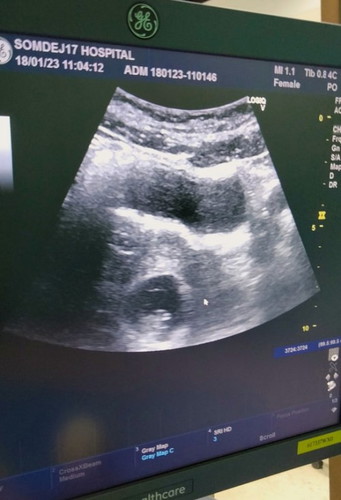

เจอตัวและหัวใจน้องแล้ว แต่ตอนนี้มีภาวะแท้งคุกคาม

วันนี้ถ้านับจากวันแรกที่เลือดออกตอนแท้งท้องที่แล้ว ท้องนี้ก็อายุครรภ์ได้ 8 สัปดาห์ 4 วัน แต่ในเครื่องซาวด์ยังไม่แจ้งอายุครรภ์นะคะ แม่มีอาการคือมีเลือดสีน้ำตาลซึมออกมา2วันติดๆ ไม่เยอะแต่กังวลเลยรีบมาหาหมอ เมื่อวานดันไปเจอหมอที่ขึ้นชื่อเรื่องตรวจพลาดและเห็นแก่ตัว ตรวจแล้วถามจะฝากพิเศษกะเขาไหมพอเราบอกไม่แกก็บอกแท้งไปแล้วหรือไม่ก็ไม่เคยท้องเลยซาวด์ไม่เจออะไรเลย(แกรูดเบาๆ2ทีเป็นใครก็ไม่เจอเนาะ 55555) แม่ก็จิตตกร้องไห้ไปสิคะ วันนี้เลยไปใหม่ไปเจอหมอคนที่รับฝากครรภ์ตั้งแต่แรก สรุปเจอน้องและหัวใจกระพริบๆค่ะ แต่เลือดยังออกนิดๆเลยโดนฉีดยากันแท้งไป1เข็มเหมือนตอนท้องลูกคนแรกเลย ตอนนี้ทำได้แค่นอนเยอะๆเดินน้อยๆ ใครที่เจอเหตุการณ์เดียวกันขอให้สู้ๆและผ่านมันไปด้วยกันนะคะ ✌️✌️#แท้งคุกคาม #เลือดออก #ภาวะแท้งคุกคาม